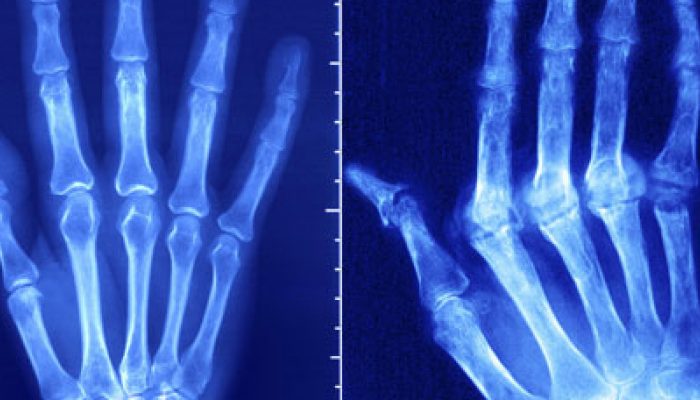

Основополагающая роль в правильной диагностике суставной патологии отводится рентгенографии. Ранним характерным рентгенологическим симптомом аутоиммунного ревматоидного артрита является выявление остеопороза в области суставных поверхностей костей. Кроме того, при рентгенографии можно определить следующие патологические нарушения:

- Сужение суставной щели.

- Суставные области костей становятся нечёткими и неровными.

- По краям костей обнаруживаются эрозии.

- В случае тяжёлого течения наблюдается разрушение эпифизов костей.

- Развитие множественных анкилозов суставов (полная потеря подвижности) – считается финальной стадией болезни.